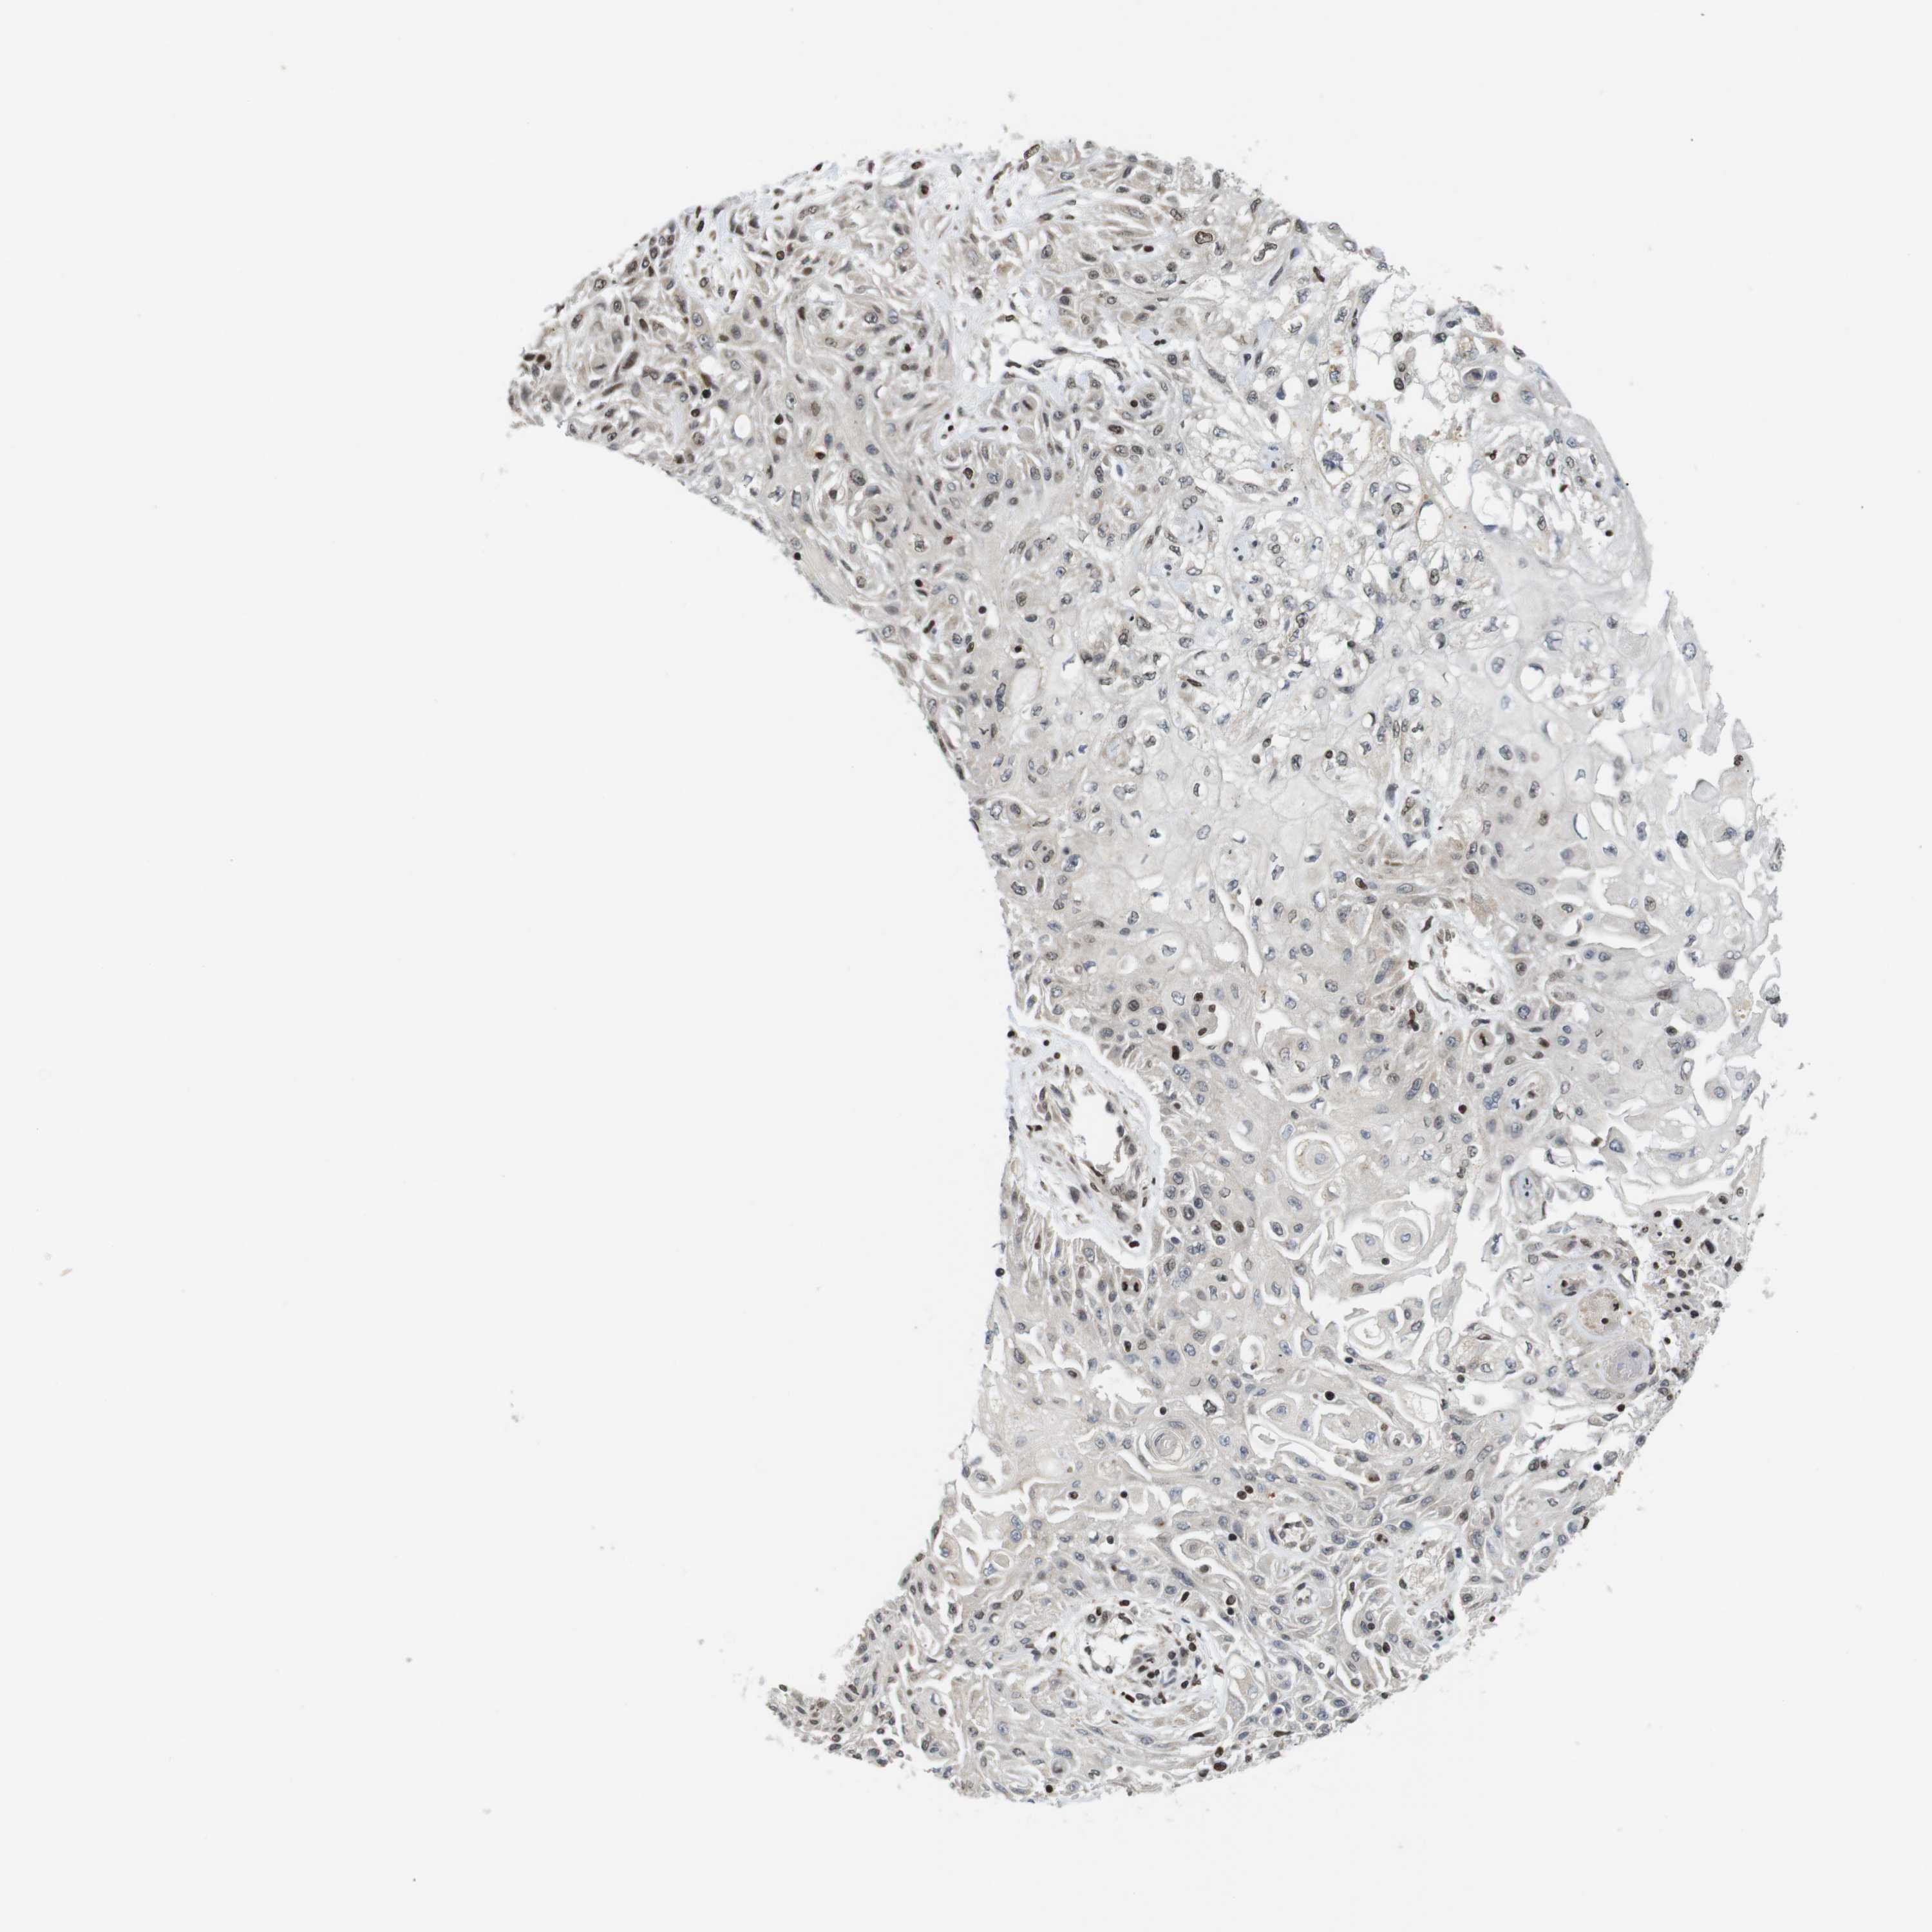

SKIN CANCER - Protein expressioni

A mouse-over function shows sample information and annotation data. Click on an image to view it in a full screen mode. Samples can be filtered based on level of antibody staining by selecting one or several of the following categories: high, medium, low and not detected. The assay and annotation is described here.

Each image is clickable and will lead to virtual microscopy that enables deeper exploration of all samples and also displays staining intensity scores, fraction scores and subcellular localization as well as patient and tissue information for each sample.

Antibody CAB036003

Staining

Not detected

Negative

None

Basal cell carcinoma